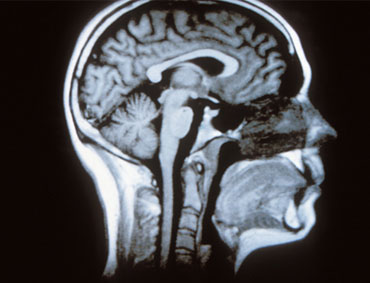

CSF is the clear and colourless fluid that cushions and delivers nutrients to your central nervous system (CNS). The CNS consists of the brain and spinal cord.

CSF is produced by the choroid plexus in the brain and then reabsorbed into your bloodstream. The fluid is completely replaced every few hours. In addition to delivering nutrients, CSF flows around your brain and spinal column, providing protection and carrying away waste.

CSF is in direct contact with your brain and spine. Therefore, CSF analysis is more effective than a blood test for understanding CNS symptoms. However, it’s more difficult to obtain a spinal fluid sample than a blood sample. Entering the spinal canal with a needle requires expert knowledge of the spine’s anatomy and a clear understanding of any underlying brain or spinal conditions that might increase your risk of complications from the procedure.